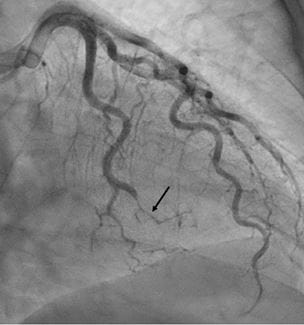

iSCAD Registry Aims to Accelerate Research

University Hospitals is one of nine national registry sites - Innovations in Cardiovascular Medicine & Surgery | Winter 2020